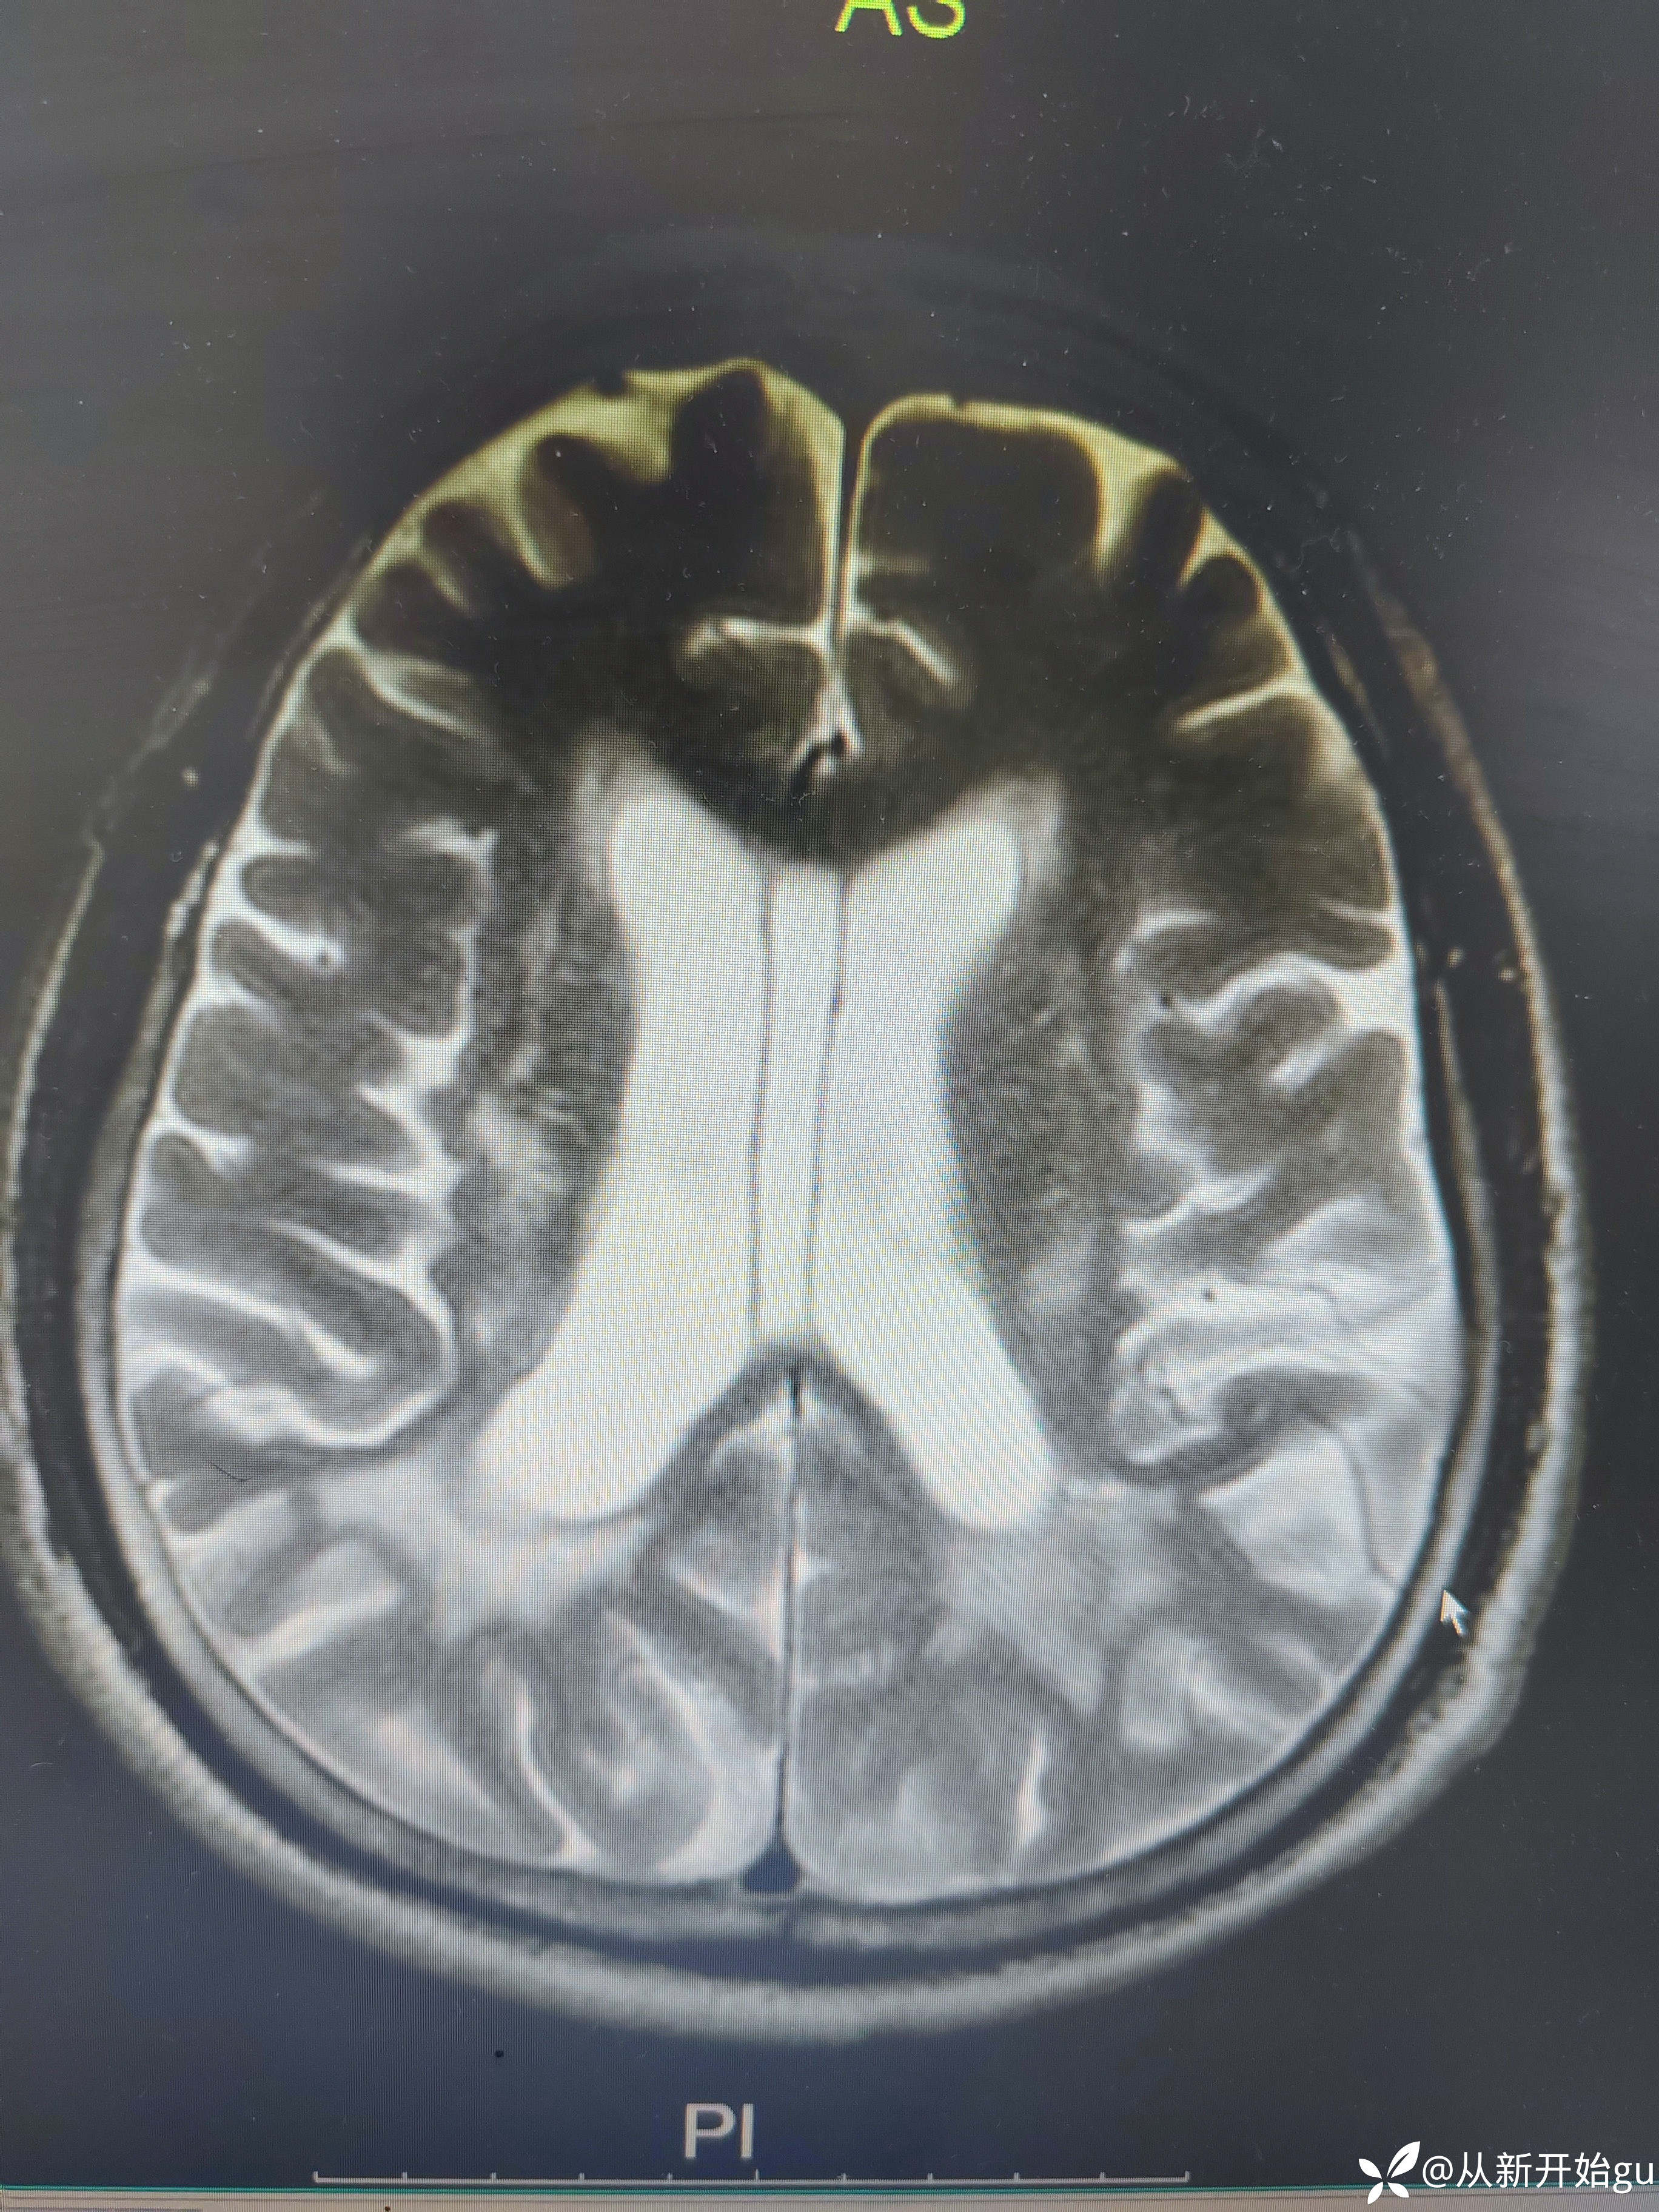

患者男性53岁,主因被发现左下肢活动障碍2.5小时来院,(患者下夜班,于上午9点休息,下午3点醒后出现症状)。既往脑梗死病史9个月,遗留言语不利及口角歪斜的症状。查体:右侧鼻唇沟稍浅,神舌右偏,左侧下肢肌力4级,左侧指鼻试验欠稳准,左侧巴氏征阳性。外院完善颅脑CT无出血改变。来院后完善核磁检查如图所示。